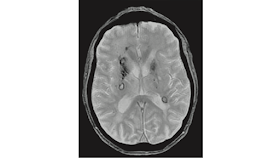

(A) Brain MRI performed on October 12, 2012. (A.a) FLAIR (FLuid Attenuated Inversion Recovery) sequence. (A.b) T1 gadolinium enhanced sequence. Routine MRI scan during fingolimod therapy shows some periventricular juxtacortical FLAIR white-matter hyperintensities with no gadolinium enhanced lesions. (B) Brain MRI performed on August 29, 2013. In the FLAIR sequence, diffuse and confluent white-matter hyperintensities are found in both hemispheres in the periventricular and subcortical white matter, with the involvement of the “U” fibers. Many lesions show gadolinium enhancement. (C) Brain MRI performed on October 17, 2013. One month after cyclophosphamide IV administration. FLAIR white-matter hyperintensities are significantly reduced (C.a) and no lesion display gadolinium enhancement (C.b) compared with the MRI performed on 29th of August (B). (D) Brain MRI performed on January 3, 2014. A remarkable increase in the number and size of white-matter hyperintensities can be observed (FLAIR sequence, D.a) compared with the scan of 17th of October. New diffuse and rim gadolinium enhancing lesions are present (D.b).

A) RM cerebral realizada el 12 de octubre de 2012. (A.a) FLAIR (FLUID Attenuated Inversion Recovery) secuencia. (A.b) secuencia con gadolinio T1. La exploración de rutina por resonancia magnética durante la terapia con fingolimod muestra algunas hiperintensidades de la materia blanca FLAIR periventriculares y de tipo liso, sin lesiones de realce de gadolinio. (B) RM cerebral realizada el 29 de agosto de 2013. En la secuencia FLAIR se encuentran hiperintensidades difusas y confluentes de materia blanca en ambos hemisferios en la sustancia blanca periventricular y subcortical, con la implicación de las fibras "U". Muchas lesiones muestran realce de gadolinio. (C) RM cerebral realizada el 17 de octubre de 2013. Un mes después de la administración de ciclofosfamida IV. Las hiperintensidades de color blanco de FLAIR se reducen significativamente (C.a) y ninguna lesión muestra realce de gadolinio (C.b) en comparación con la RM realizada el 29 de agosto (B). (D) RM cerebral realizada el 3 de enero de 2014. Se puede observar un notable aumento en el número y tamaño de hiperintensidades de la materia blanca (secuencia FLAIR, D.a) en comparación con la exploración del 17 de octubre. Están presentes nuevas lesiones de aumento de gadolinio difuso y de borde (D.b).